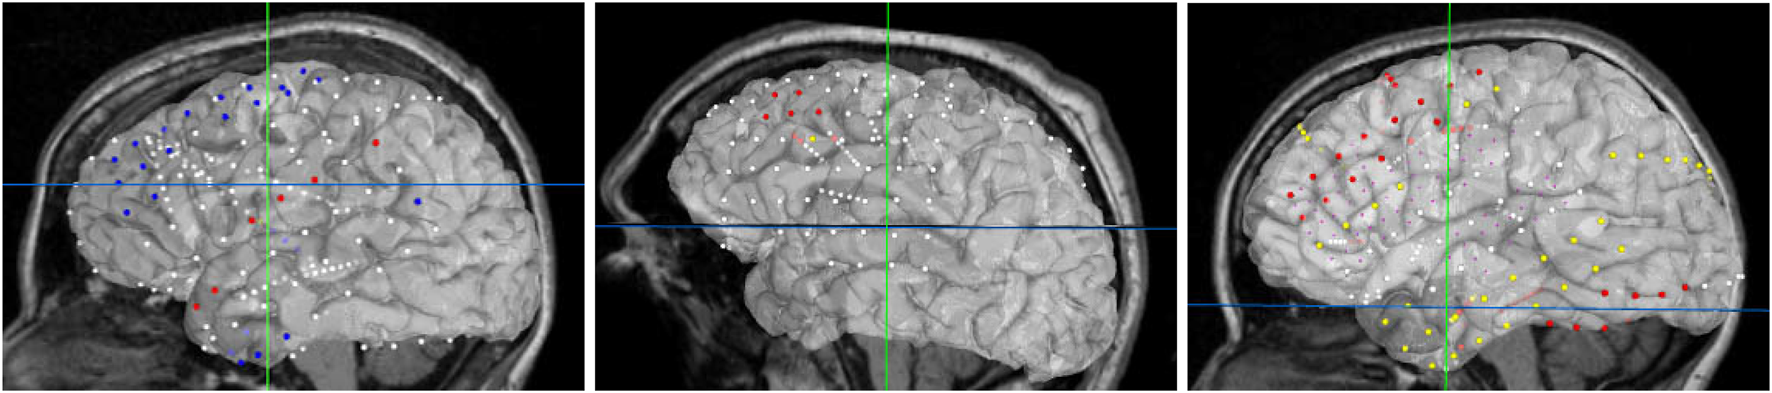

For best usability, we designed our user interface to show all the relevant information of an electrode in one panel. Figure 5 shows an example where a user has highlighted electrode G27, as well as a functional map in the category of “motor”. The information regarding the seizure type of an electrode is displayed, and the note for the selected functional map. Since G27 has no seizure type, no caption is displayed for seizure type or interictal population. New connections will be drawn if the user selects an alternative functional map. The user can also press the “Show All Tags” button to display the caption of each electrode, as seen in Figure 6. Finally, Figure 7 shows the complete finished rendering of three subjects.

Information displayed about an electrode (G27) and functional mapping when clicked by a user. Selecting a functional map from the drop down menu will display the connected electrode pairs involved.

Brain surface mesh with all electrode IDs displayed simultaneously.

Final browser-based visualization of three different subjects NY704, NY758, NY836 including localization of electrodes on the brain surface. The color of each electrode represents the different attribute (onset, early spread, etc.) for the corresponding seizure type.